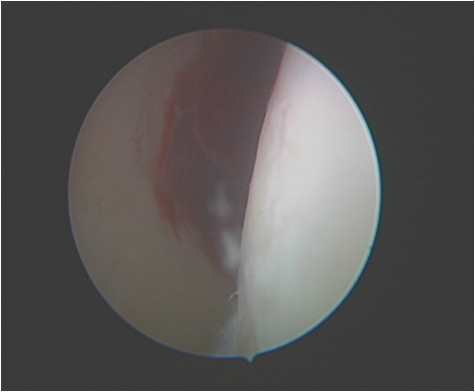

肩关节镜手术